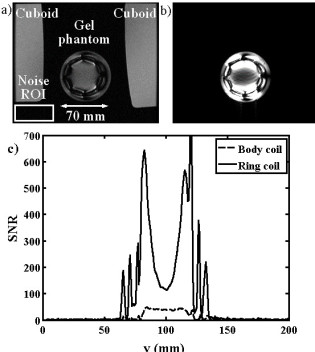

Richard Syms, Evi Kardoulaki and Ian Young

Simon Taylor-Robinson, Chris Wadsworth and Marc Rea (St Mary’s Hospital)

We have developed a magnetic resonance imaging duodenoscope, by combining non-magnetic endoscope components with a thin-film receiver based on a magneto-inductive waveguide. The waveguide elements consist of figure-of-eight shaped inductors formed on either side of a flexible substrate and parallel plate capacitors that use the substrate as a dielectric. Operation has been simulated using equivalent circuit models and by computation of sensitivity patterns. Circuits have been fabricated for operation at 127.7 MHz by double-sided patterning of copper-clad Kapton and assembled onto non-magnetic flexible endoscope insertion tubes. Operation has been verified by bench testing and by 1H MRI at 3T using phantoms. The receiver can form a segmented coaxial image along the length of the endoscope, even when bent, and shows a signal-to-noise-ratio advantage over a surface array coil up to three times the tube diameter at the tip. Initial immersion imaging experiments have been carried out and confirm an encouraging lack of sensitivity to RF heating.

| Arrangement for magnetic resonance imaging with cuboid phantoms (a), body coil image showing effective decoupling (b) and metamaterial coil image, showing segmented field of view (c). |

| Results of Magnetic resonance imaging at 1.5 T: axial slice images obtained using a) the body coil and b) the sensor; c) variation of SNR with vertical position obtained using the two coils. |